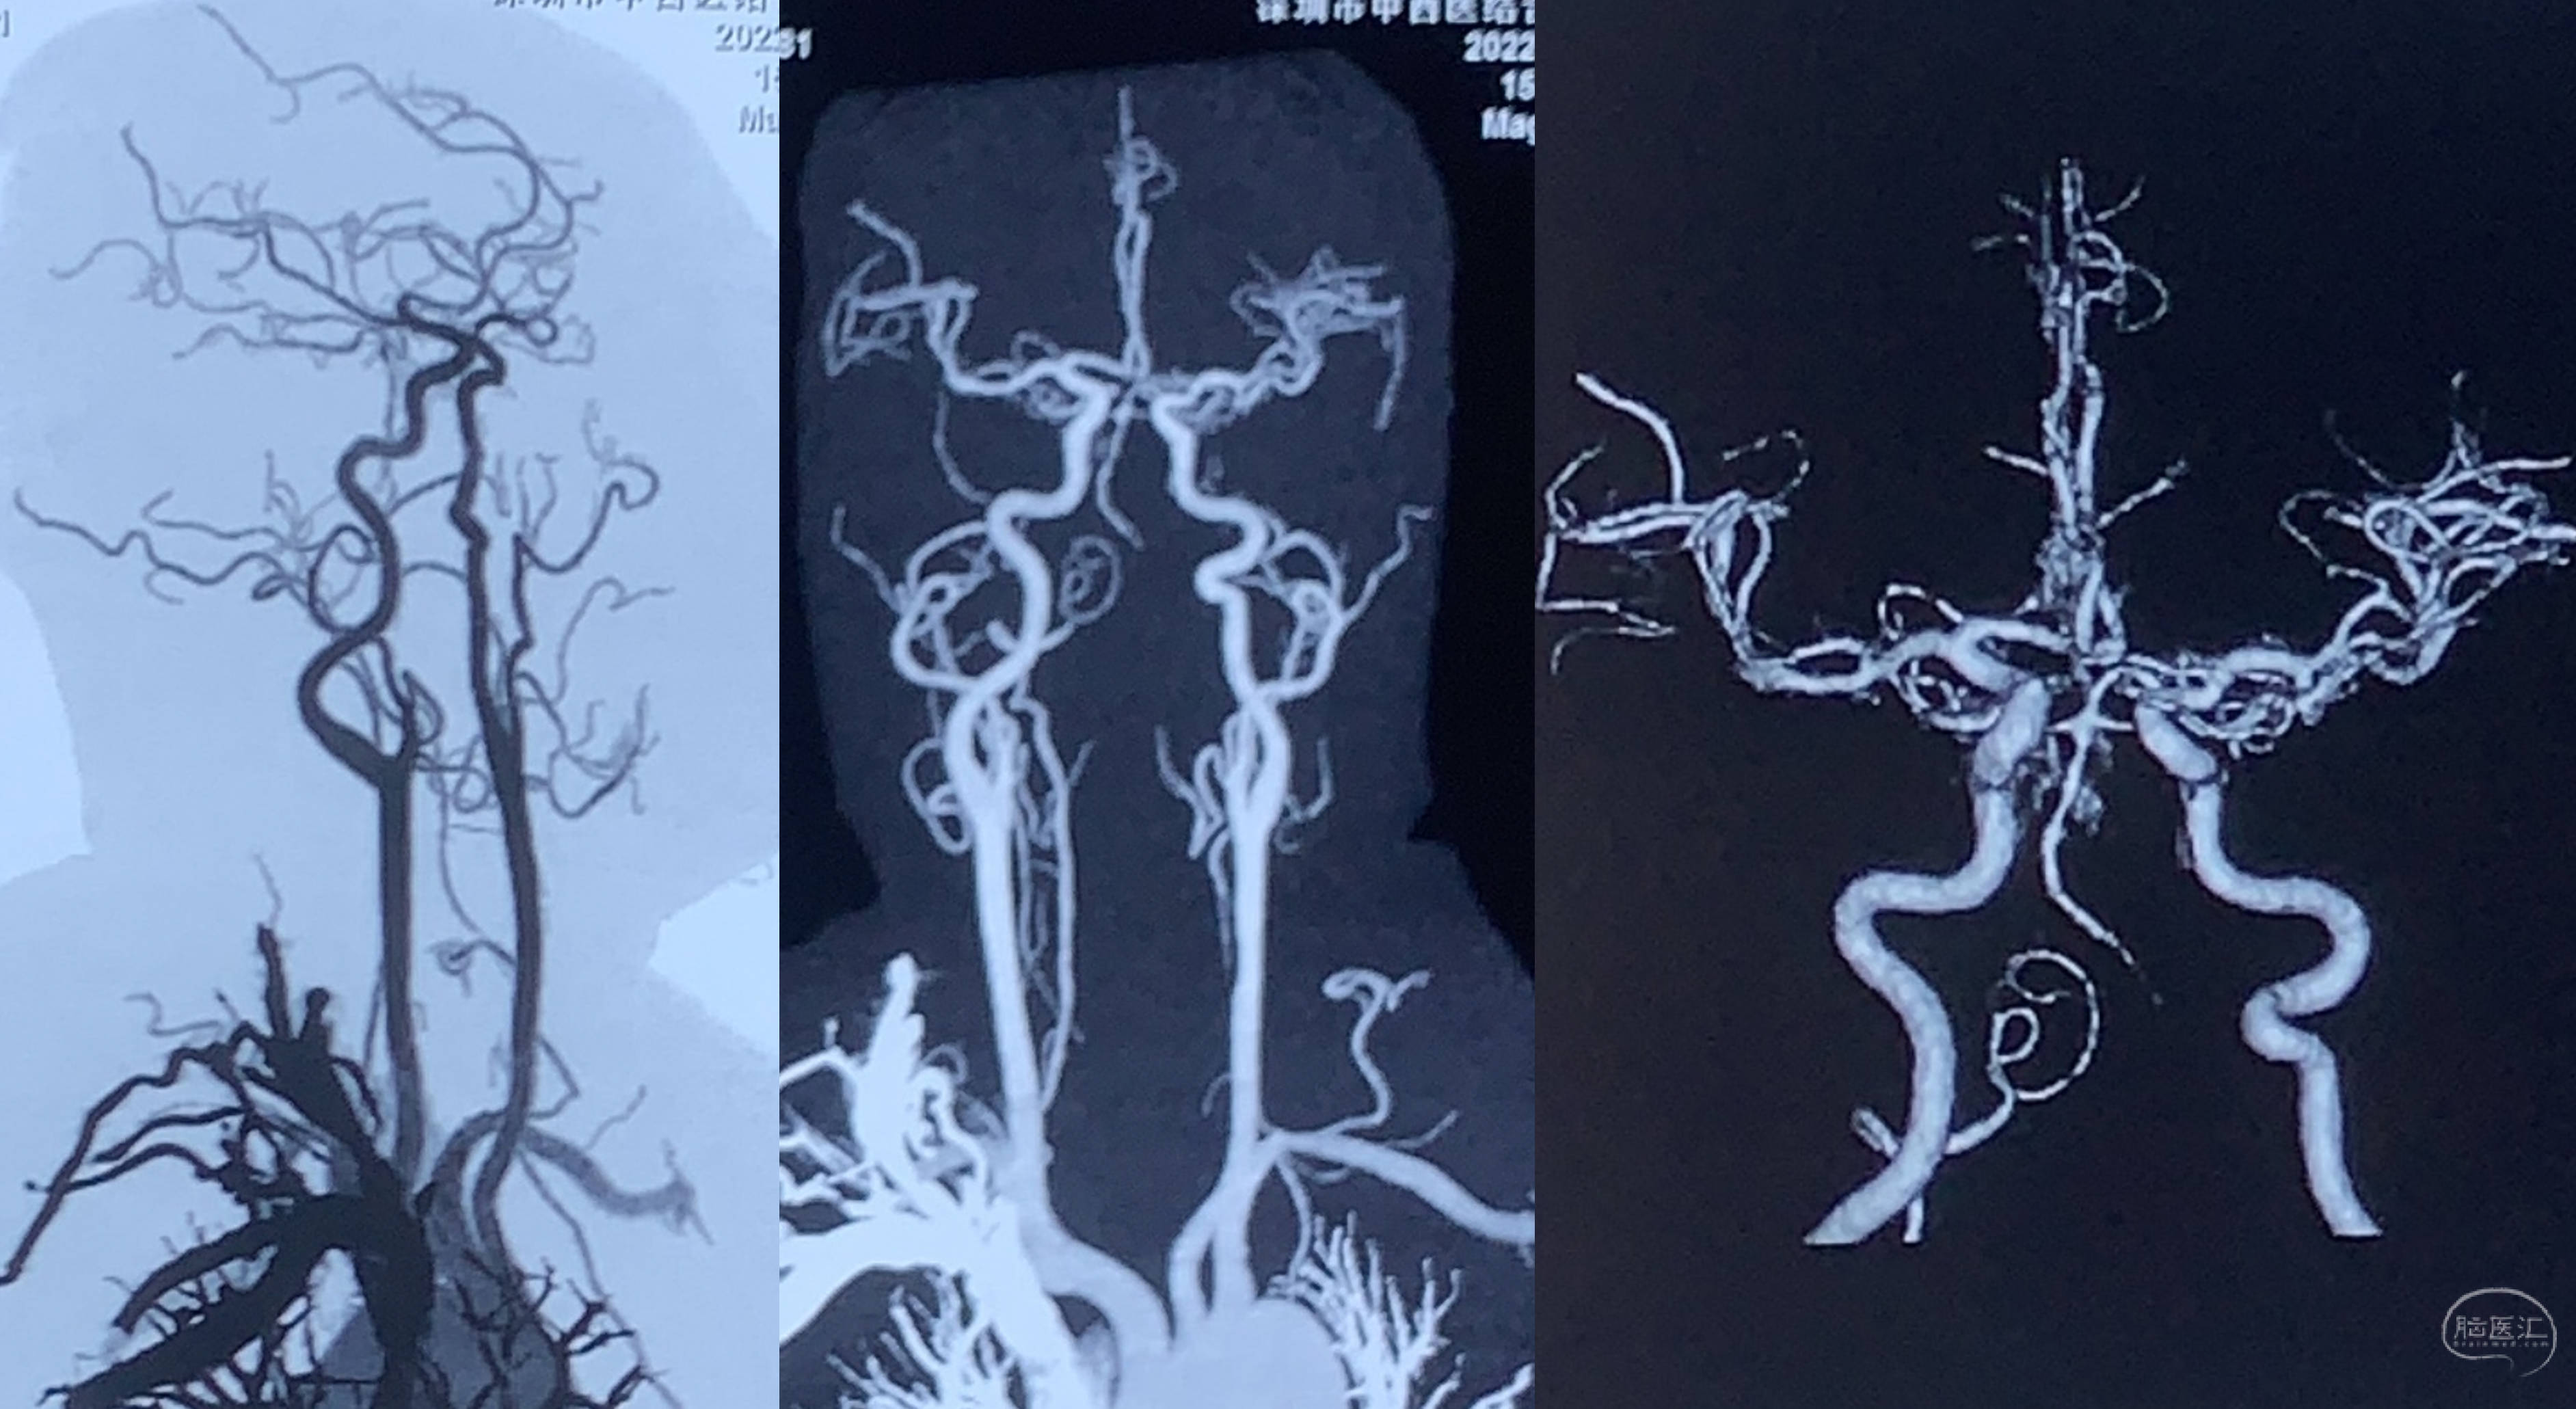

MRA提示左侧椎动脉闭塞,右侧发育不良,颅内段重度狭窄。

入院后的CTA确认闭塞,右侧VA发育不良!

左侧V4段显影,但V3段会不会随着时间推移形成血栓?(距离外院治疗已经2个月)如果闭塞的话,OA-V3搭桥的方案可能就行不通了!替代方案为枕下开颅,OA-PICA bypass!